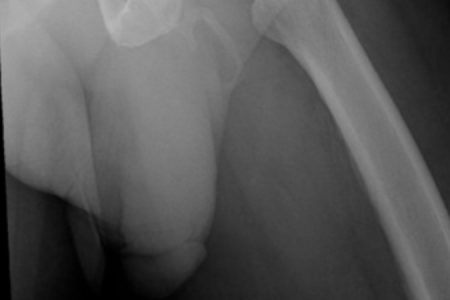

Y los extraños resultados, mostraron que su pene se estaba convirtiendo en hueso, por lo que se veía nítido en los rayos X. Tan particular resultó ser esta patología que incluso terminó suiendo publicada en la revista Urology Case Reports.

«La osificación del pene, una condición rara, se ha relacionado con la enfermedad de Peyronie. La osificación se lleva a cabo generalmente en la mitad del eje del pene con pocos casos en todo el eje, como en éste» se puede leer en el estudio.